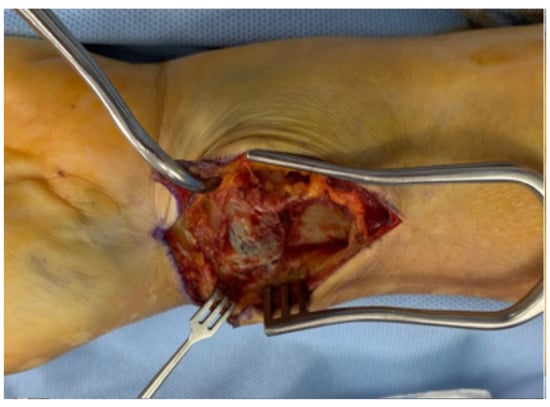

The superficial layer of the FCR sheath is longitudinally incised, and the FCR tendon is retracted ulnarly to protect the median nerve (Figure 2). The antebrachial fascia and the deep layer of the sheath are then exposed and opened (Figure 3). Adequate proximal exposure of the sheath is essential, and the distal floor should be opened carefully to avoid neurovascular injury.

Figure 3. Medial retraction of the FCR; exposure of the antebrachial fascia.

Surgeries 06 00104 g003